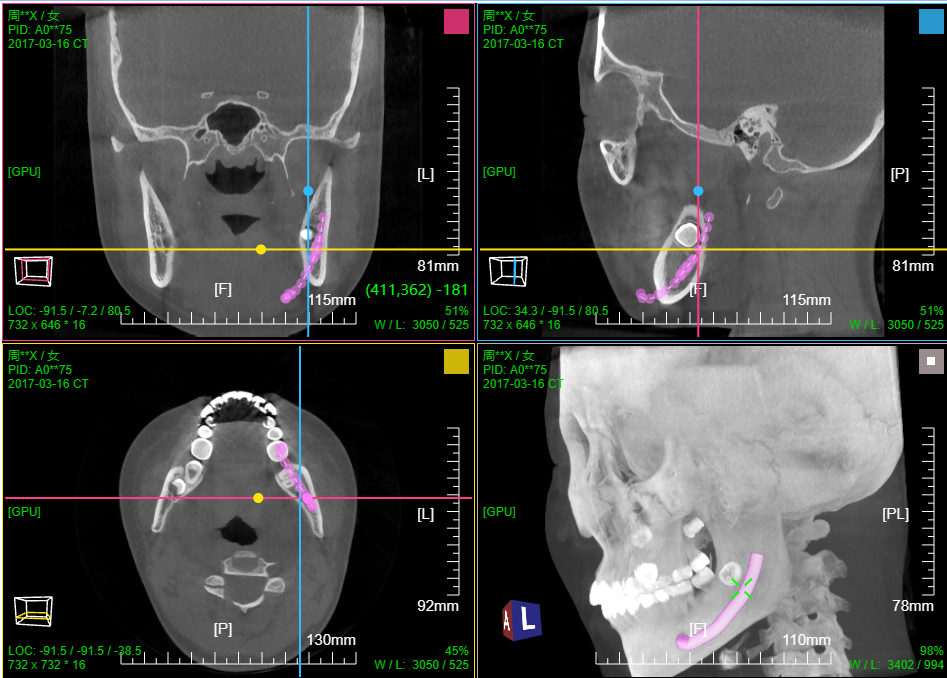

十、血管CPR曲面拉伸拉直

打开血管增强造影序列; 菜单 选择 "路径点手工标记"

在MPR切片上选取2个血管中心点,确定血管起始位置和前进方向

菜单 选择 "血管中心辅助提取"

滚轮下滚则则沿当前方向前进自动检测下一个血管中心位置和检测到的大小(图示5 圆为检测血管半径,红点为中心; 绿点为重建血管垂直切面中心)

滚轮上滚则回退并删除当前检测的血管中心点

鼠标滚轮在重建血管垂直切面右侧(图示3)上下滚动 则调整切面X轴方向以便切面和血管垂直, 在MPR上可看到该切面和血管的交线(绿线)

鼠标滚轮在重建血管垂直切面下侧(图示4)上下滚动 则调整切面Y轴方向以便切面和血管垂直, 在MPR上可看到该切面和血管的交线(绿线)

鼠标左键按下并移动则拖动改变当前检测血管中心点的位置,滚轮在检测点(红点)上滚动则调整检测的血管半径大小(仅仅确定前进步长用)

点击自动前进并检测(图示2) 则程序自动沿血管中心路径前进并检测记录中心点位置;如果检测失败则停止前进,需手工干预调整

注:自动检测前进时 还可通过包围盒裁剪设定检测截至范围

血管中心检测提取结束后,菜单 选择 "血管CPR拉直渲染"

窗口1:MPR窗口

窗口2:血管CPR拉伸; 窗口3:血管CPR拉直; 窗口4:当前血管位置(绿线)垂直重建切片和前后切片

滚轮在窗口2和窗口3上滚动可调整 当前血管位置(绿线, 图示5)

滚轮在窗口2和窗口3 右侧上下滚动 则可沿血管中心360旋转CPR

窗口2:血管CPR拉伸 支持厚切,可开启厚切

也见视频操作录像

血管中心辅助提取_CPR拉伸拉直渲染